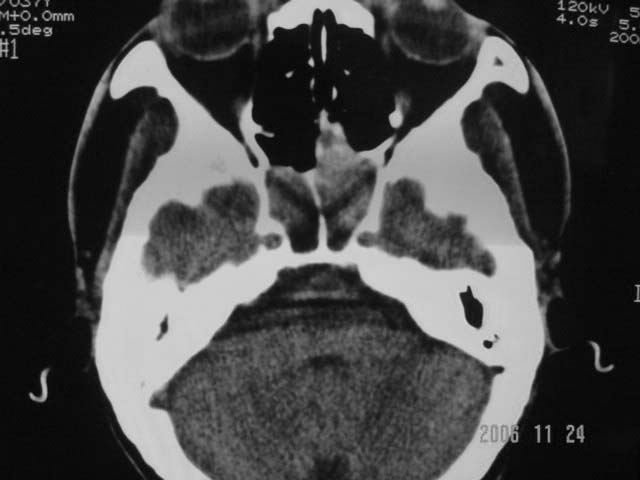

右侧鼻咽部软组织肿块,颅底骨质破坏,右侧颈部淋巴结肿大;诊断:鼻咽ca、右颈部淋巴结转移、颅底侵犯

右侧鼻口咽侧后壁不规则增厚,内可见密度不均匀性椭圆形软组织块影,边界欠清,咽旁间隙尚清.右颈部可见圆形软组织块影,鼻塞、耳鸣3个月,涕中带血2周,颈部可触及肿大淋巴结,考虑鼻咽癌,颈部淋巴转移.

右侧鼻咽后壁不规则增厚,内可见密度不均匀性椭圆形软组织块影,边界欠清,咽旁间隙尚清.右侧下方可见圆形软组织块影,双侧蝶窦呈均一高密度。

考虑:1、右侧鼻咽癌伴颈部淋巴结转移;

2、双侧蝶窦炎。

右侧鼻咽部软组织肿块,颅底骨质破坏,右侧颈部淋巴结肿大;诊断:右侧鼻咽ca伴右颈部淋巴结转移、颅底侵犯.

典型右侧鼻咽ca伴颈部淋巴结转移,中颅底骨侵蚀。

右侧鼻咽侧后壁不规则增厚,咽隐窝变钝,咽旁间隙变狭窄,见组织结节影[哨兵征],蝶骨似破坏,蝶窦内充塞软组织影,翼内外肌上分间隙模糊,右颈后三角区淋巴结肿大,右侧乳突增高气房消失。考虑鼻咽癌伴蝶窦侵犯及淋巴结转移,右侧浆液性中耳炎。其他恶性病变待排。